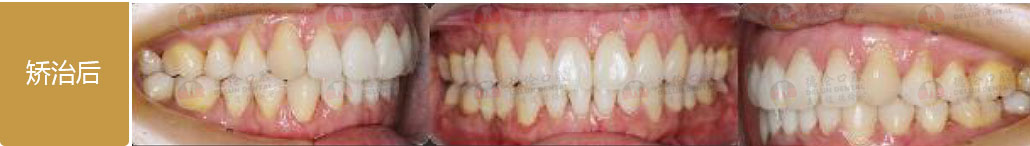

- 【診斷】

先天缺少下切牙2顆

上前牙錯(cuò)位于下前牙后側(cè),前牙無(wú)咬合功能,上牙槽及上唇后縮

打造醫(yī)生:德倫口腔正畸中心鄧毅醫(yī)生

- 【治療方案】

調(diào)整弓形及配合Ⅲ類牽引,實(shí)現(xiàn)頜跳躍

矯治前后對(duì)比

牙列整平排齊,前牙內(nèi)收;覆蓋、覆合正常;尖牙和磨牙達(dá)到中性關(guān)系;上下中線對(duì)齊;下頜后縮改善